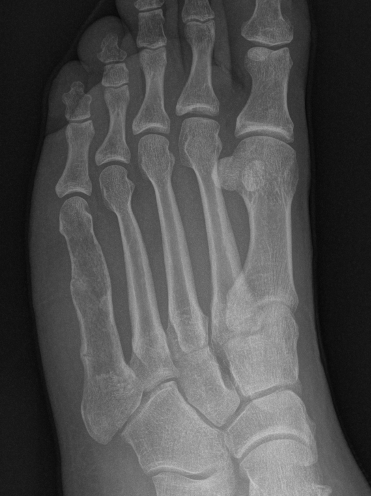

- tubular bones of hand and feet

Hand / Foot

Foot